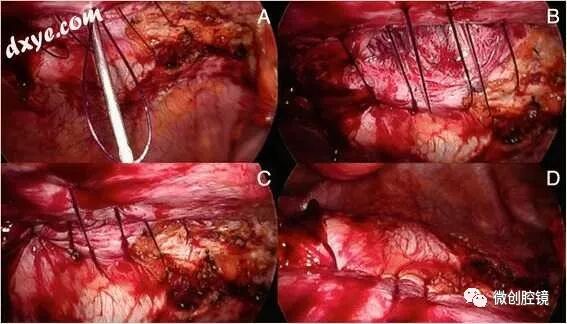

图14左侧Spigelian疝的TEP修复。 a)腹壁缺损; b)左侧外侧腹膜外剥离术(LCF:股外侧皮神经; FB:生殖 - 股神经的股骨分支;

PM:腰肌); c,d)使用Endoloop PDS对弱筋膜进行倒置和折叠(箭头); e,f)圆形聚酯网覆盖复制(箭头)Spigelian筋膜通常缺损很小,因此我建议使用PDS的Endoloops(图14c,d)d)或如前所述的可吸收1PDS的八字形(图4)进行初步闭合。使用标准的扁平聚酯或聚丙烯网片进行疝气增强就足够了,因为没有与下层内脏形成粘连的风险,但我仍然喜欢使用圆形9cm直径的PCOx网(有时是12cm的网),因为它是柔软的,倾向于自发地粘在腹腔上,预成形并且已经包含两根留置缝合线(图14e,f).f)。此外,网格与缺陷的比率使得较小的圆形PCOx尺寸足够。最后,网状物优选地用可吸收的钉固定,但是在缺陷非常小的某些情况下,单独的纤维蛋白胶也可能是足够的。无论采用IPOM,IPOM-Plus,TAPP还是TEP的技术,在检查满意的修复止血后,优先使用排水。气腹(或额外)在直视下完全放气,局部麻醉剂注入伤口,皮肤闭合,中断皮下3/0